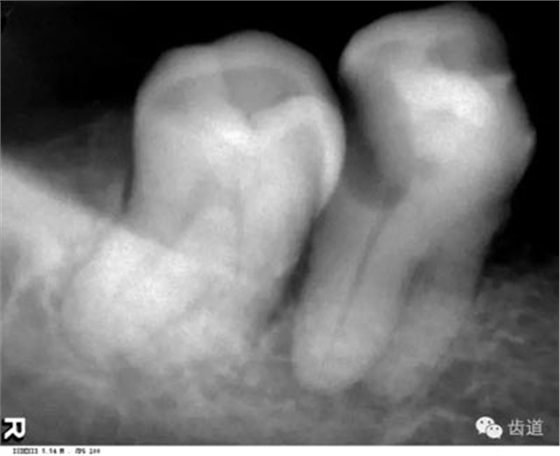

由升支前緣下部斜向前下方,為一密度高的帶狀影像。常重疊在第二、三磨牙牙冠處、頸部或根部,使牙髓室或根管不能清晰顯示